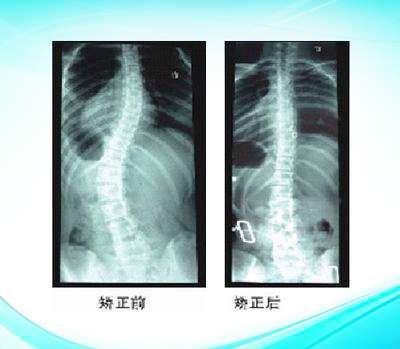

脊柱側(cè)彎矯形產(chǎn)品

色努脊柱側(cè)彎矯形器

脊柱側(cè)彎矯形器3

脊柱側(cè)彎矯形器2

脊柱側(cè)彎矯形器

波士頓脊柱側(cè)彎矯形器...